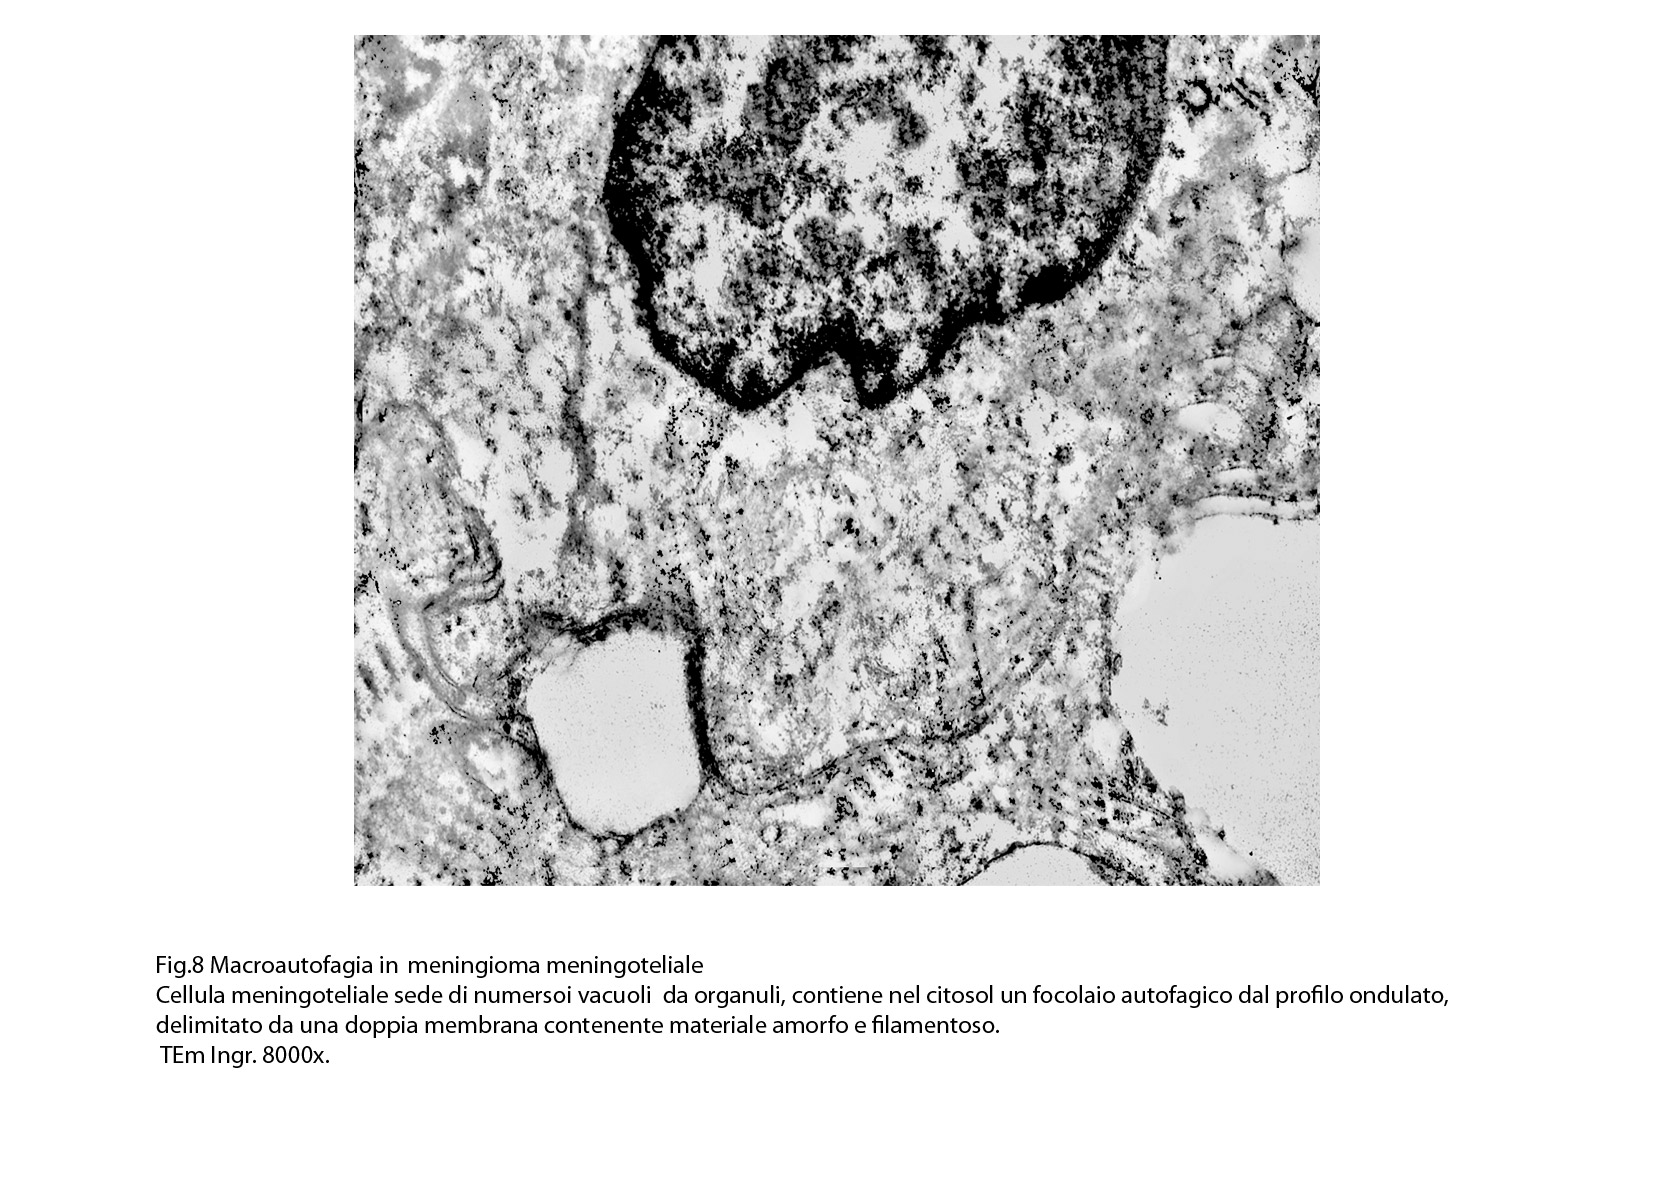

I focolai di macroautofagia possono essere presenti in zone diverse del citoplasma. La loro microstruttura di base è costituita da una area vacuolare demarcata da una membrana a doppio strato; l’area cava è occupata per quote variabili da materiale amorfo,da aggregati filamentosi,da frammenti di organuli,da gruppi granulosi, il tutto in diversi stati di conservazione. Questi focolai macroautofagici appaiono come strutture avulse dalle mutevoli condizioni bio-morfologiche del citoplasma nel quale si sono formate. E’ frequente il riscontro di cellule di aspetto cribroso per la esistenza di micro vacuoli scavati nel citosol e per la dilatazione delle cisterne del reticolo endoplasmico contengano nel citosol una formazione macroautofagica occupata in parte da materiale amorfo e filamentoso.

Non mancano elementi cellulari,forniti di un citosol contenente solo ribosomi liberi, rare strutture reticolo endoplasmatiche in via di disgregazione e molto materiale amorfo, essere occupati da un focolaio di macroautofagia con aggregati di filamenti.

Sono repertabili anche cellule meningoteliali ben strutturate e ricche di organuli marcate da un focolaio di autofagia contenente frammenti di substrutture e materiale filamentoso.

Anche a livello di prolungamenti citoplasmatici di cellule meningoteliali si riscontra la presenza di due focolai autofagici occupati in parte da materiale amorfo.